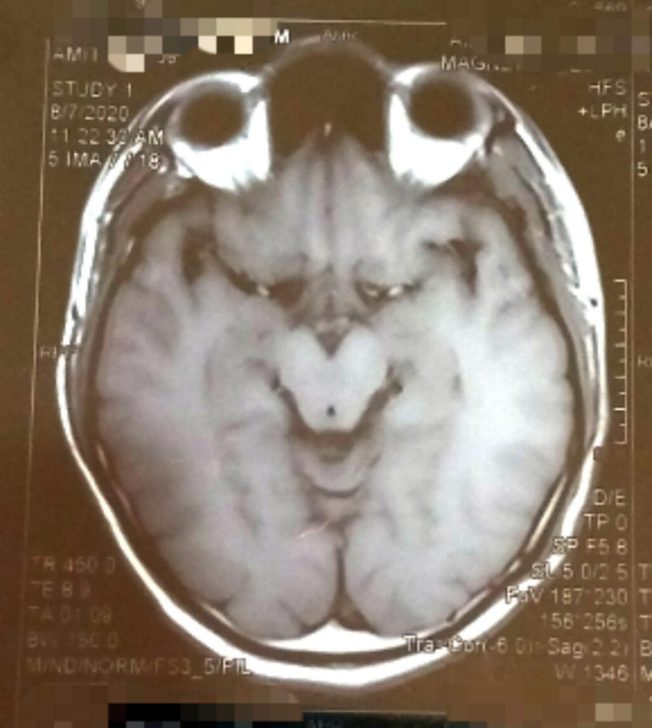

„Az agyam MRI-je olyan, mint a Grinch”